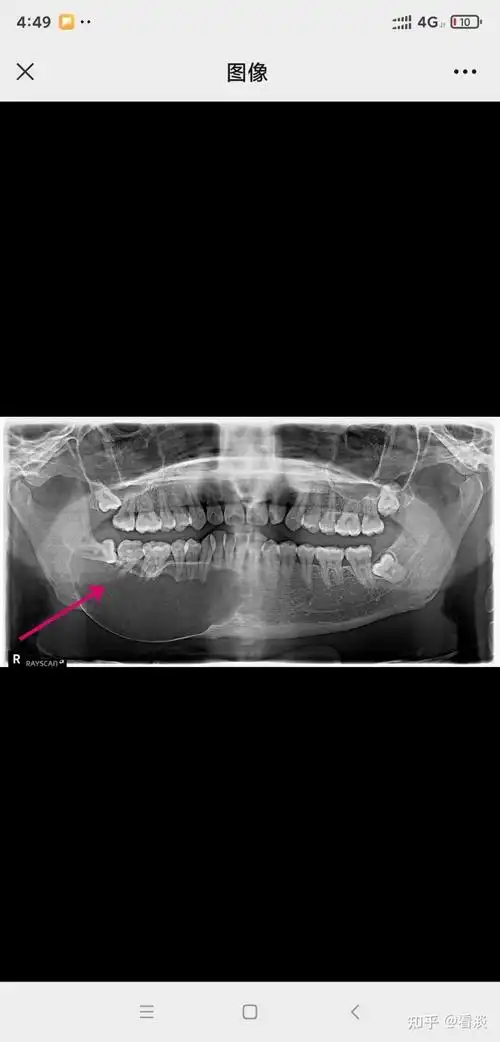

cbct提示右下颌的囊肿